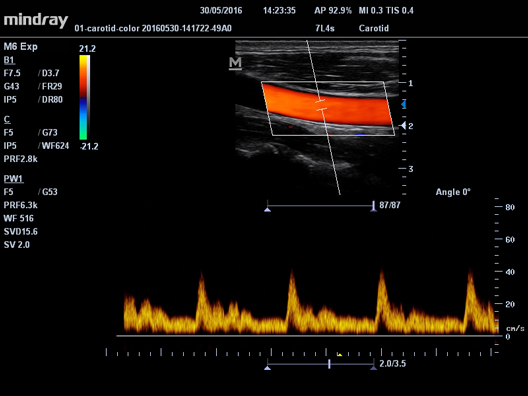

Auto IMT

Автоматическая детекция и вычисление толщины комплекса интима-медиа сонной артерии. Опция Auto IMT позволяет получить точную и эффективную оценку состояния стенки сонной артерии.

Auto IMT

Автоматическая детекция и вычисление толщины комплекса интима-медиа сонной артерии. Опция Auto IMT позволяет получить точную и эффективную оценку состояния стенки сонной артерии.